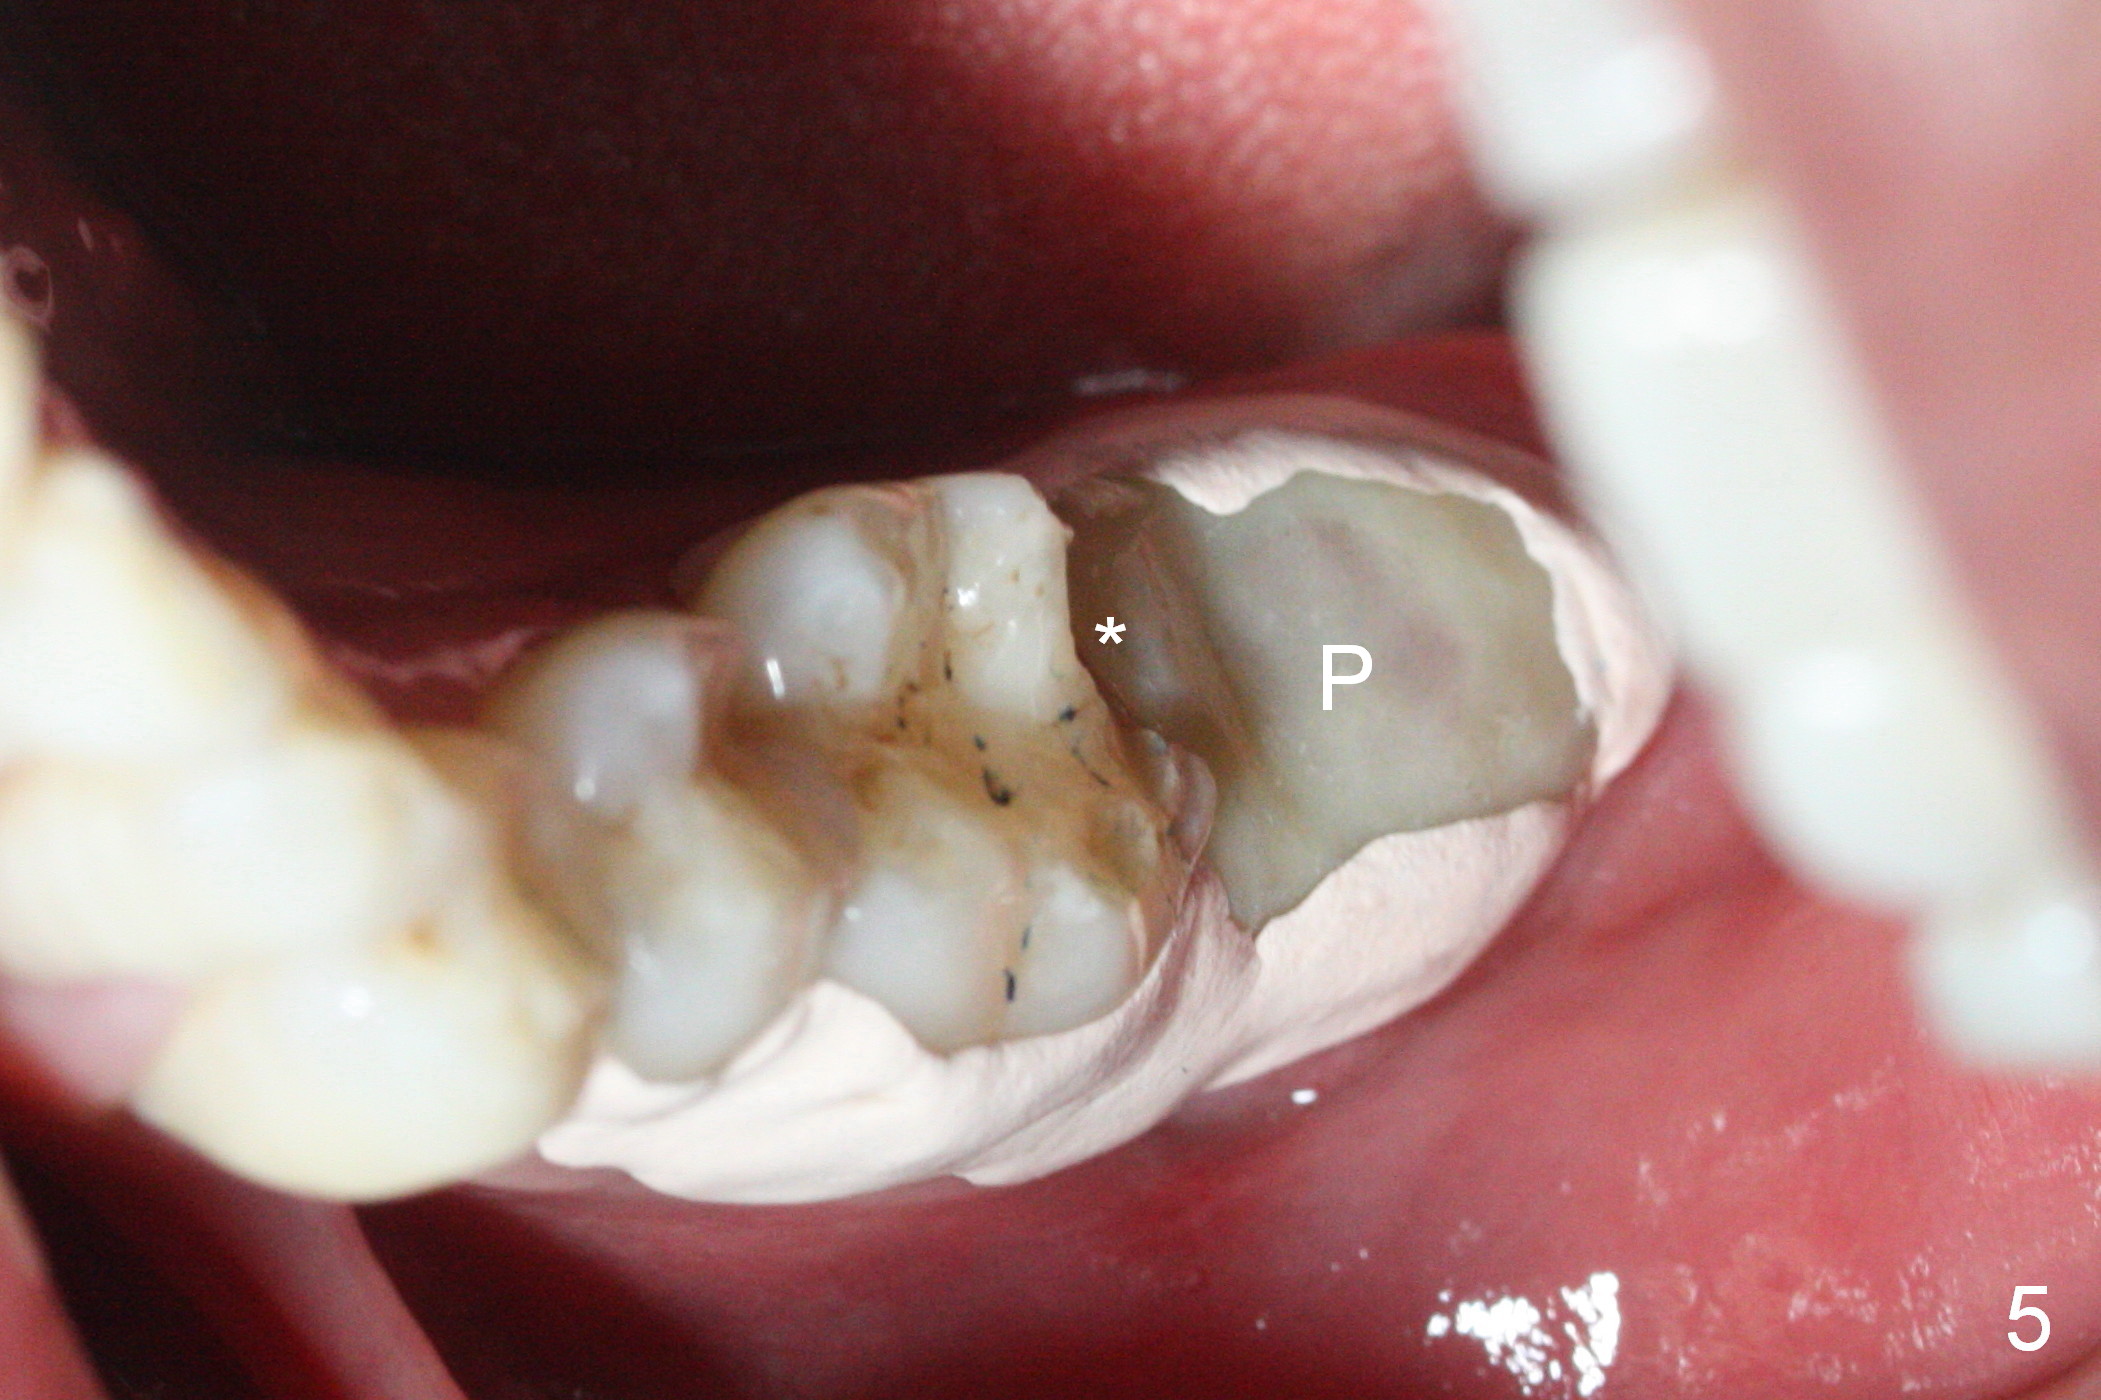

When the tooth #18 is extracted, the buccal and lingual plate are absent. Initial osteotomy is established in the middle of the socket (Fig.1). After 4.3 mm Magic Drill (15 mm from the buccal gingival margin, new bone ~ 4 mm), a 5x9 mm IBS dummy implant is placed with correct trajectory (Fig.2). Since the bone density is seemingly high, the same size of a definitive implant is placed with primary stability. The trajectory is found not ideal after bone graft and insertion of an abutment (data not shown). The stability is lost when the trajectory is changed. No primary stability is achieved with a larger (5.5x9 mm) implant. Tatum tapered taps (6x17, 7x17 and 8x17 mm) are used. The latter obtains stability with contact with the mesial and distal crests (Fig.3 *). A 8x14 mm tissue-level implant is placed with insertion torque ~ 55 Ncm (Fig.4). A 6x3 mm abutment (Fig.4 A) is placed to retain an immediate provisional (Fig.5 P). The drawback of the extra large implant is lack of bone buccolingually. Oral hygiene is emphasized so that the buccal and lingual bone have chance to regenerate. Fortunately there appears to be no paresthesia postop.

It appears that the patient chews on the left postop, since the provisional perforates with loose abutment nearly 3 months postop and the tooth #3 has occlusal sensitive chip. The implants seems to have osteointegrated (Fig.6). To improve oral hygiene, the provisional is not recemented. The patient will return for impression in 2 weeks. It appears that there is short healing time for large implant. There is no bone loss 7 months post cementation (Fig.7). The buccal gingiva is lightly erythematous without tenderness 1 year 7.5 months post cementaion. Water pik is being used, although chronic periodontitis is not under control. Retrospectively, surgery should be shifted to socket preservation when a moderate implant (5 or 5.5 mm) fails to achieve primary stability. The extra large implant (8 mm for example) leaves a little gap buccolingually. Guided surgery would allow precise placement of the moderate implant without change in trajectory. The crown becomes loose because of occlusal perforation and limited vertical space. When a new crown is cemented, the bone density around the coronal threads is high (Fig.8 *). While the bone remains stable at #4 (6 months post RCT), 13 (4 years 6 months post cementation) and 18 (2 years 5 months post cementation), there is severe bone loss at #2 and 31 (Fig.9).